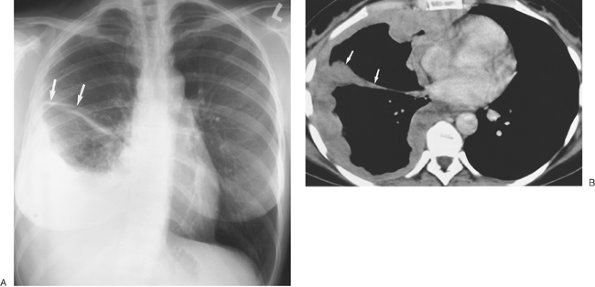

FIGURE 9-5. Cerebrospinal fluid leak into pleural space. A: PA chest radiograph of a 42-year-old man who recently underwent partial corpectomy of the thoracic spine at several levels shows complete opacification of the right hemithorax and shift of the mediastinum to the left. B: Non–contrast-enhanced CT shows a large right pleural effusion, collapse of the right lung, mediastinal shift to the left, findings of corpectomy, and continuity of fluid from the spine into the pleural space (arrow).